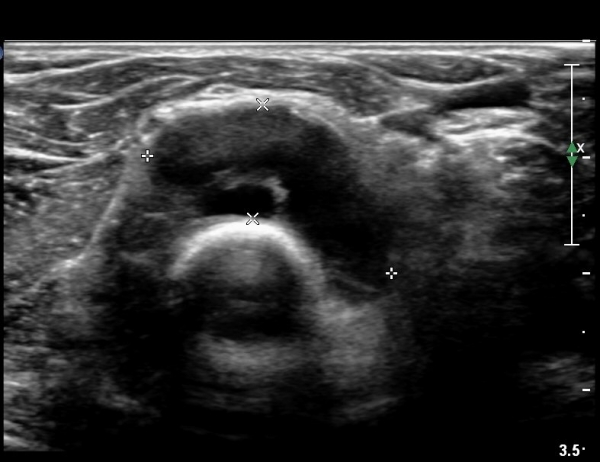

¿Ü»ó°ú¿¡¼­ ¼Õ¸ñ ½ÅÀü°Ç ´ÜµÎ Á¾´Ü¸é°Ë»ç¿¡¼­ ƯÀÌ ¼Ò°ßÀ» º¸ÀÌÁö ¾Ê´Â´Ù(»çÁø 1, 2)

¿ä°ñµÎ ºÎÀ§ ÆÈ²ÞÄ¡ ¾Õ, ¿ÜÃø Ⱦ´Ü¸é°Ë»ç¿¡¼­ Èİñ°£ ½Å°æ ³»Ãø, ¿ä°ñµÎ Ç¥Ãþ¿¡¼­

ÀÛÀº ³¶Á¾ÀÌ °üÂûµÈ´Ù(»çÁø 3)

ŽÃÊÀÚ¸¦¸»´ÜÀ¸·Î  À̵¿ÇÏ´Ï ¿ä°ñ¸ñ ºÎÀ§¿¡¼­ Ä¿´Ù¶õ ³¶Á¾ÀÌ Èİñ°£ ½Å°æÀ» ¾Ð¹ÚÇÏ´Â °ÍÀÌ

°üÂûµÈ´Ù(»çÁø 4, 5)